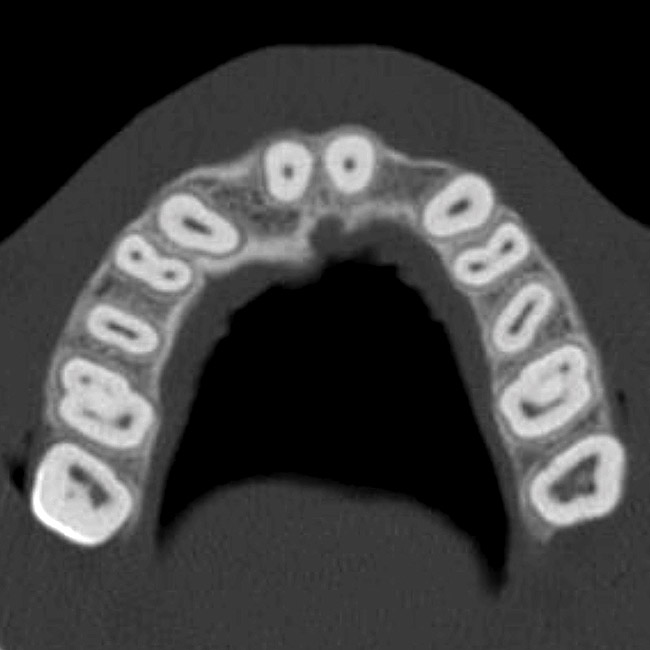

The CT axial views represent an important instrument in gaining a better understanding of anatomical features that cannot be determined by any other imaging modality (Figure 10). When the maxilla is sliced axially at the level where the roots meet the crest of the bone, the adjacent and surrounding root morphology can be revealed. Of note are the individual and different shapes of each of the central incisors, canines, premolars, and molar roots. These images reflect a phenomenon defined by the author as the “restorative dilemma.” Clinicians encounter this often difficult dilemma when attempting to re-establish morphologically correct emergence profiles in prosthetic teeth as they ascend from the round shape of the implant(s). When planning for the placement of the implant in the left lateral incisor area, there appeared to be adequate mesial-distal space between roots as seen in the axial view of Figure 11. A closer inspection of the planned site for the right lateral incisor revealed a more narrow space, further complicated by the distal rotation of the palatal aspect of the tooth root. Based on this preliminary position, the 3.75-mm diameter, straight-walled implant can be seen encroaching on the lamina dura periodontal ligament space of the right canine and central incisor. If there was not adequate room for this diameter and type of implant, the adjacent teeth could sustain potential iatrogenic damage. Therefore, additional “tweaking” of the virtual placement was necessary to diminish this risk.

Figure 10  SOFTWARE IMAGING By slicing the maxilla axially, the images revealed the differing morphology of the central incisors, canines, premolar, and molar roots.

Figure 10

Figure 11  SOFTWARE IMAGING  The left simulated implant can be seen encroaching on the adjacent lamina dura.

Figure 11